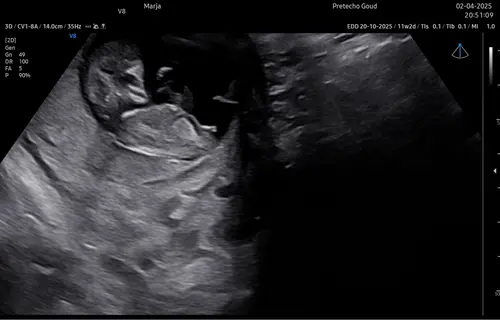

Dit is de tweede

Eerste zie je niks. Deze echo is een jongen! 💙

Dat is echt geen jongen dat is een meisje 😉 dat is de clitoris die je ziet

Ik denk toch ook meisje nub te zien hierop😁 wanneer heb je geslachtsecho?